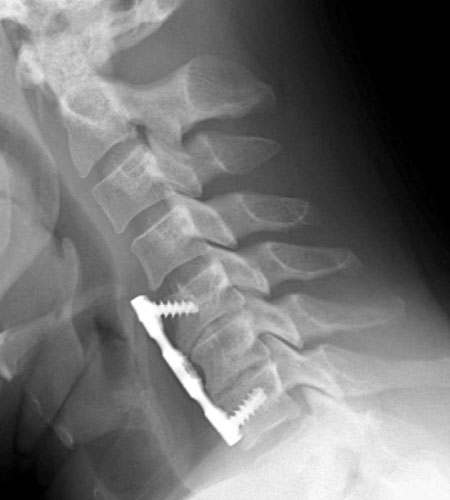

Lateral radiograph taken six weeks later on routine follow-up demonstrates

loosening of the superior anterior screws and ventral displacement of

the proximal anterior plate. Early incorporation of grafting material can be

seen at the disc spaces. |